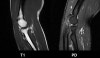

팔꿈치 관절의 MRI 단면 영상

1. Coronal section

1) Collateral ligament

2) Common extensor/flexor tendon group patholgy as well as epicondylitis